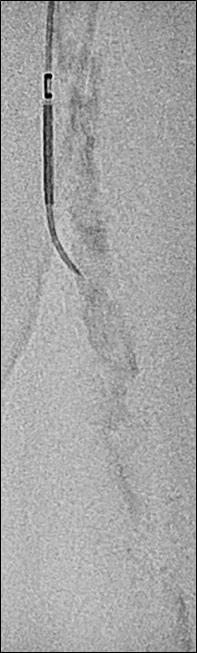

Crossing chronic total occlusion lesions are challenging procedures. The BeBack crossing catheter—Bentley’s first product to be available in both Europe and the USA following the company’s acquisition of Upstream Peripheral Medical Technologies’ GoBack crossing catheter in September 2022— offers a new solution in this space. In a Bentleysponsored advertorial, Andrej Schmidt (Leipzig, Germany) shares his clinical experience with the BeBack, noting how it has been a “gamechanger” in his endovascular peripheral arterial disease practice.

For more on this story go to page 19.